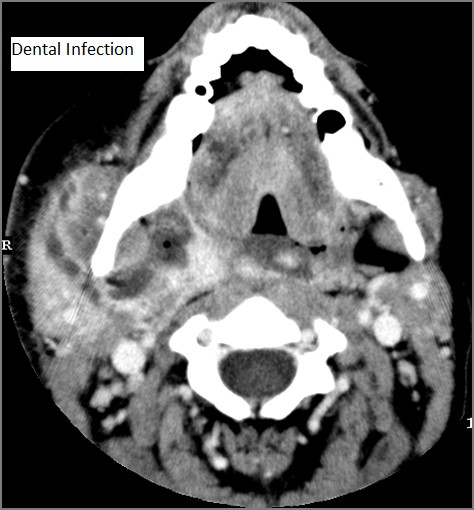

Oral Cavity, Floor of the Mouth, Maxilla and Mandible

There is significant abnormality of these structures that would be an alternate explanation for the patient’s symptoms.